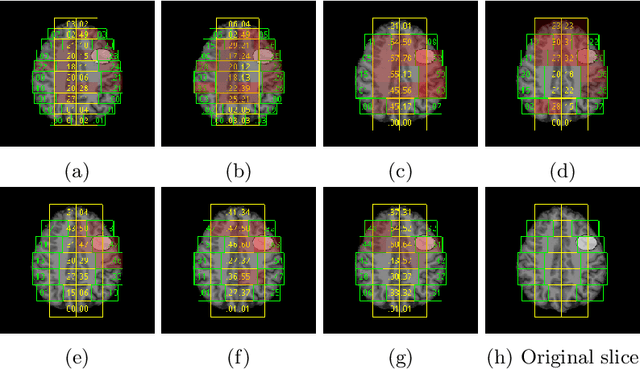

Abstract:Focal cortical dysplasia (FCD) is one of the most common epileptogenic lesions associated with cortical development malformations. However, the accurate detection of the FCD relies on the radiologist professionalism, and in many cases, the lesion could be missed. In this work, we solve the problem of automatic identification of FCD on magnetic resonance images (MRI). For this task, we improve recent methods of Deep Learning-based FCD detection and apply it for a dataset of 15 labeled FCD patients. The model results in the successful detection of FCD on 11 out of 15 subjects.